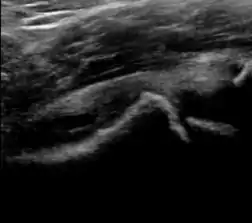

Figure 12:

Normal ultrasound appearance of the femoral head-neck junction.

Joint effusion in transient synovitis of the hip.

Flattening of the femoral head in a patient with Perthes disease.

Step in the femoral head-neck junction in a patient with SCFE.